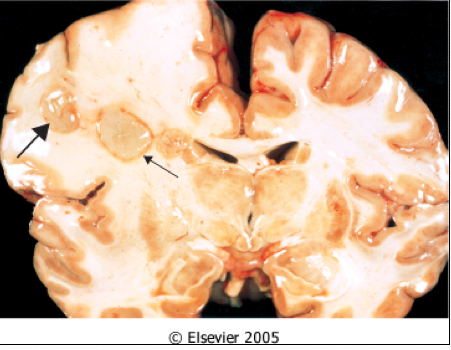

what does this image show?

Cerebral Edema:

cerebral abcesses surrounded by edema